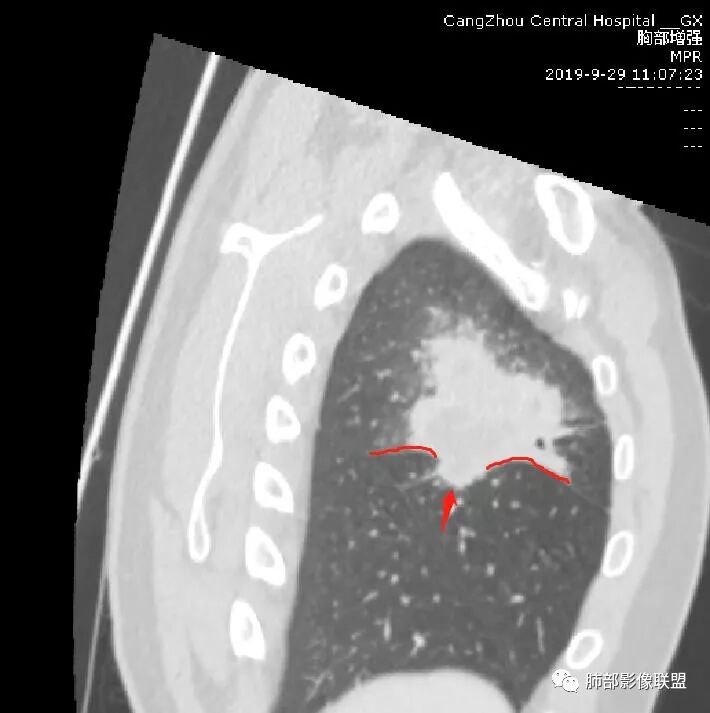

首先病灶示:跨尖、后、前三段,局部突入中叶;大家理解一下:是不是光滑的地方有叶裂,毛糙的地方没叶裂。

南边:

这个病变两侧受叶裂的局限,中央没有,如果是穿透叶裂的是否边缘也毛糙?事实上这叶裂边缘的叶裂是很光滑的,我倾向于这个是局部叶裂有缺陷;就是从缺陷处进来有病灶的本色:边缘毛糙;附近叶裂的阻挡,边缘光滑;既然怀疑是局部的缺陷就对良恶性没价值。

第二种是局部叶裂畸形或发育不全、有缺陷,病灶经缺陷处侵犯蔓延,事实上叶裂缺并非少见,影像观察应当结合冠矢状位。

假如一个病灶直接跨越胸膜侵犯过来,应该边缘都很毛糙,不应该是最突出的地方毛糙,应该是逐步毛糙过去的,充其量越到外面毛糙越少;但事实上今天这个病变是一个很突兀的毛糙,突然间嘎然而止的毛糙;所以这个提示应该是从缺陷处跨过来的;还有今天的这个病例,病灶跨叶的部分对附近的胸膜是推移的,附近的胸膜还是很光滑,但是跨叶的病灶区很毛糙,提示跨叶部分存在胸膜缺陷可能;一般来说恶性肿瘤直接侵犯到对侧还是少的,如果这个地方你怀疑有缺陷,跨胸膜在诊断良恶性价值就不大了。